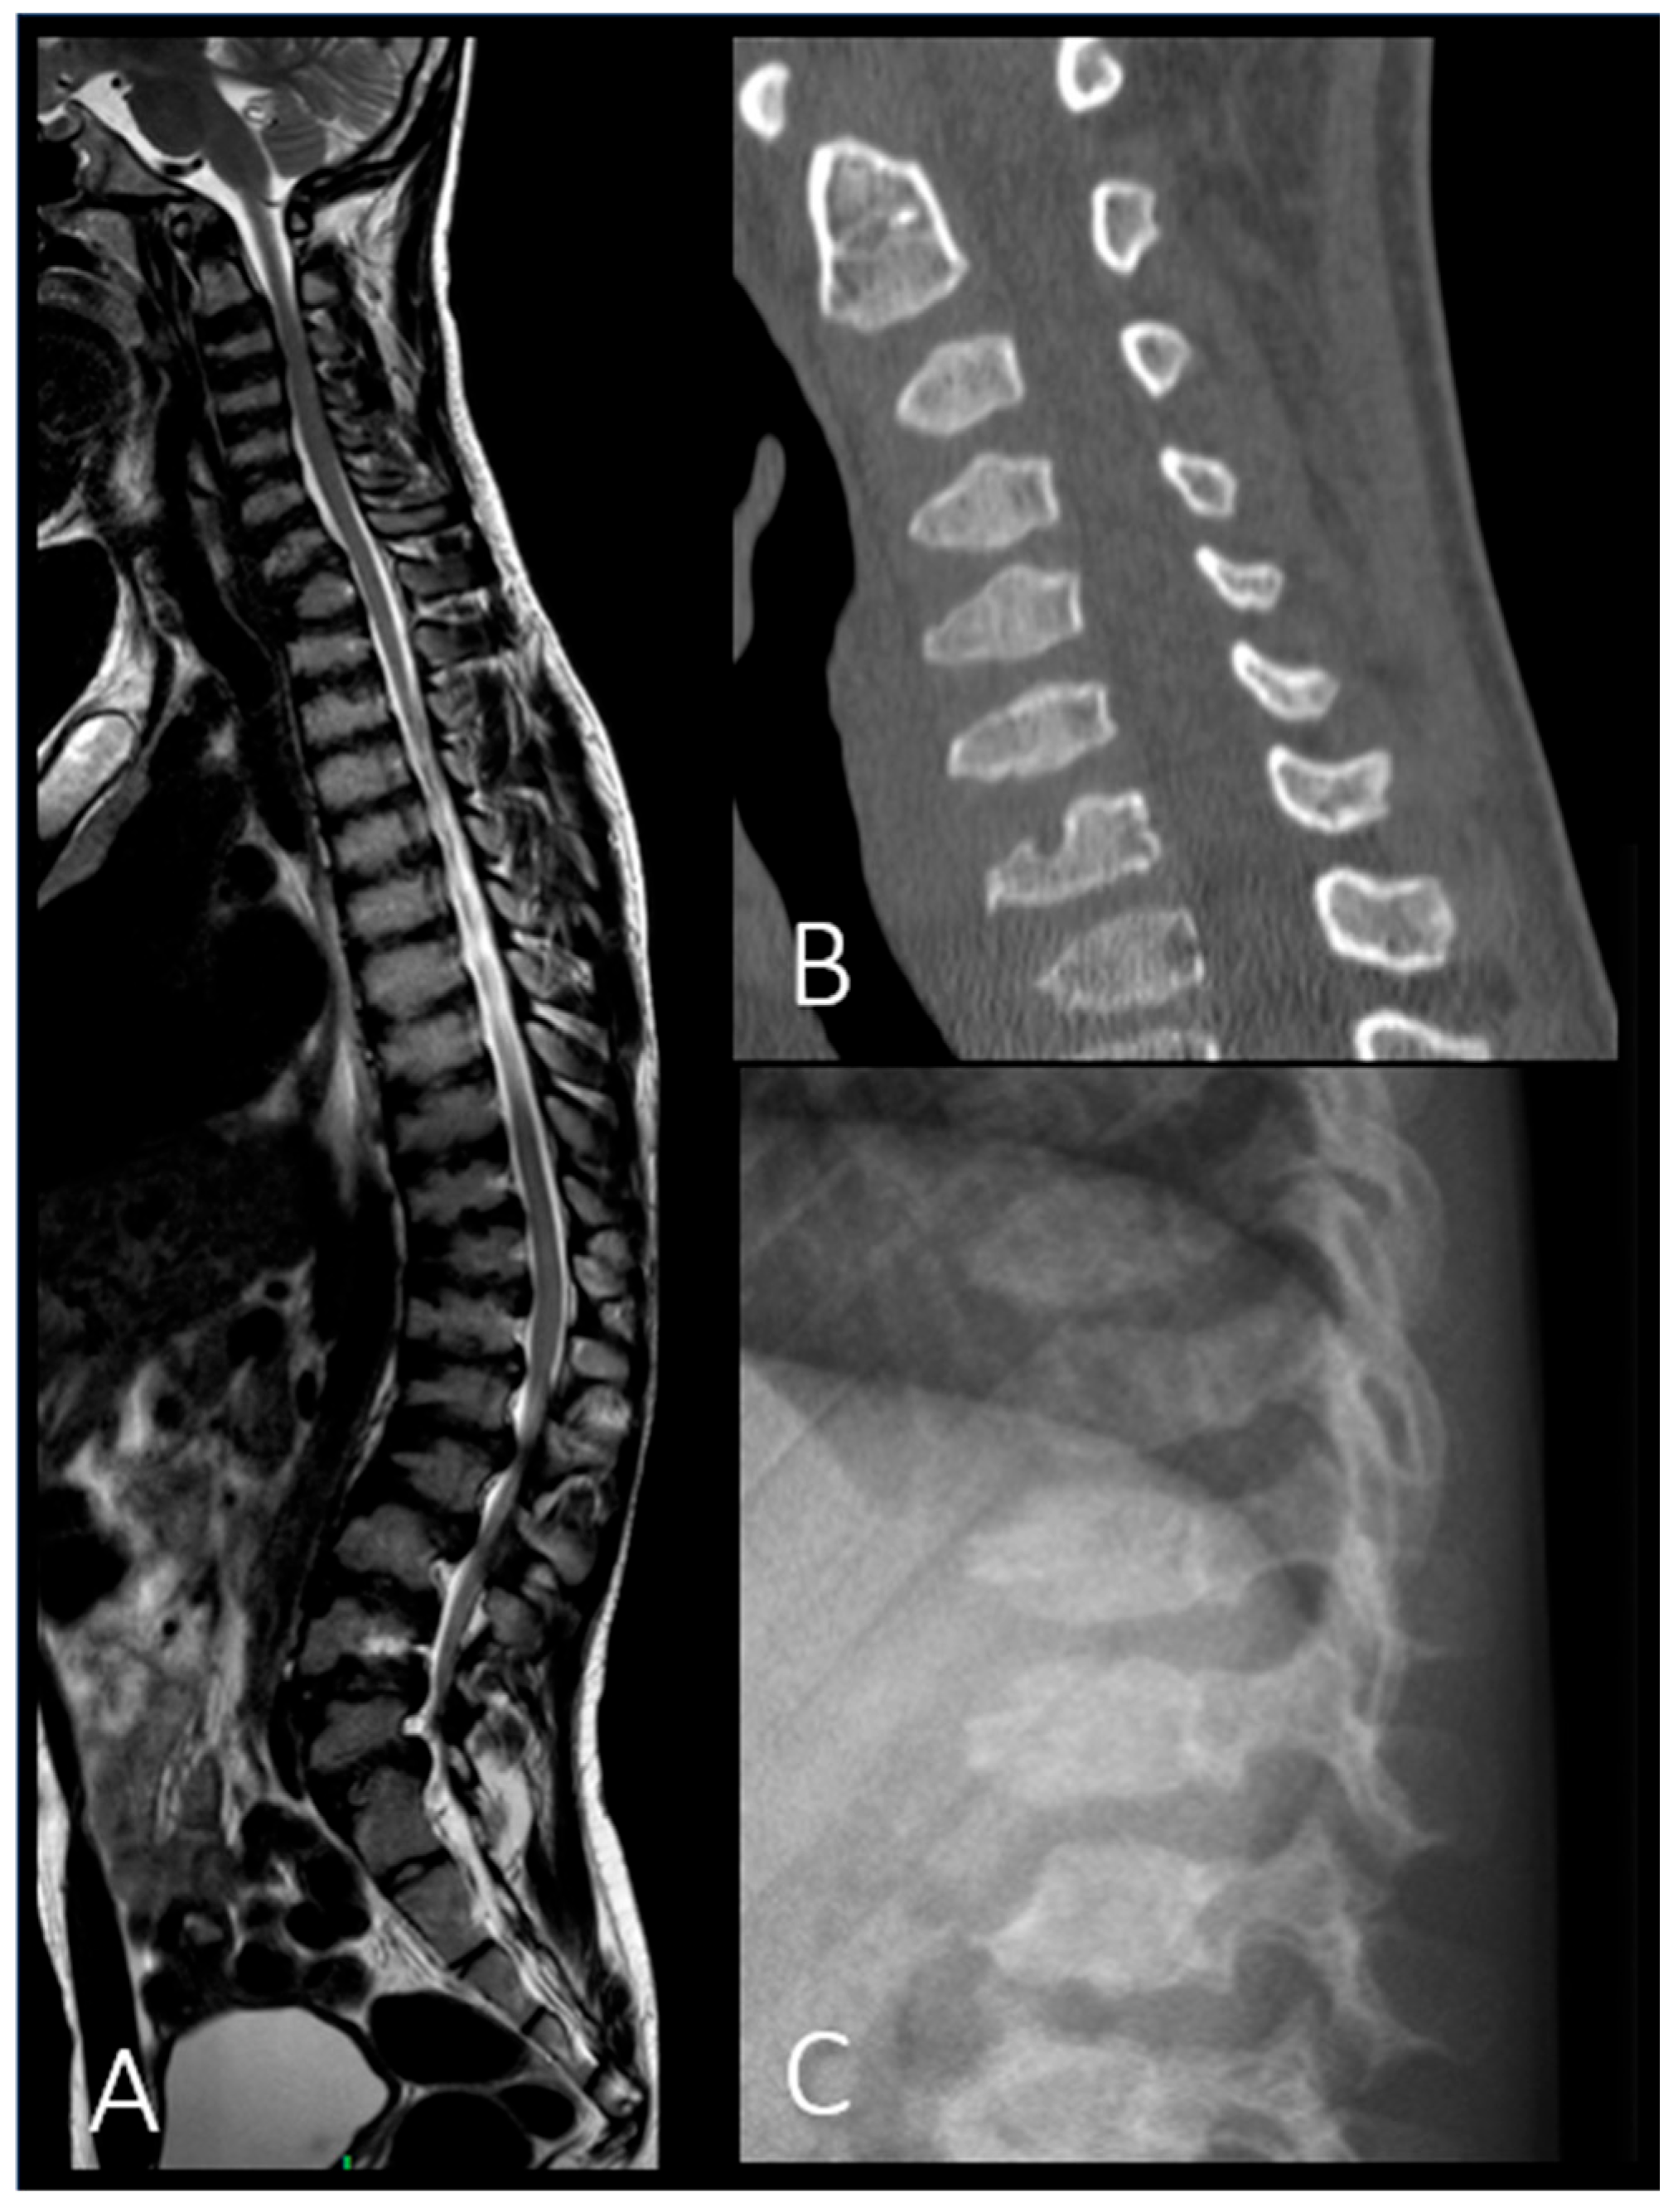

| Platyspondyly with beaking of vertebral bodies | + | + | + | + | + | + | + | + |

| Kyphosis | + | + | + | + | + | + |

| P2 (MPSII) | Baseline | RX and MRI | Spine | Vertebral body deformities; posterior bulging of the intervertebral discs. |

| After 6 years of ERT | RX and MRI | Spine | Thoracolumbar kyphosis; anterior beaking and posterior scalloping of vertebral bodies. | |

| P6 (MPSIV) | Baseline | CT | Spine | Platyspondyly in both cervical and thoracolumbar regions; anterior vertebral body beaking. |

| After 8 years of ERT | MRI | Spine | Deformities of the vertebral bodies and posterior bulging of the intervertebral discs; spinal canal impression. |